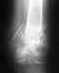

Перелом передней верхней части позвонков L2,L5

Здравствуйте!Помогите мне пожалуйста,поставили диагноз-перелом тела L2,L5 позвонка.Для уточнения давности повреждений рекомендовано проведение МРТ.

Эта травма у меня давно,спина болит постоянно,а в этот раз просто резко прострелило правую ногу,ступня почти не чувствовала.На руки дали протокол кт-исследования поясничного отдела позвоночника.Заключение написано выше.Объясните ,что может быть при наличии такой травмы, и как лечить.